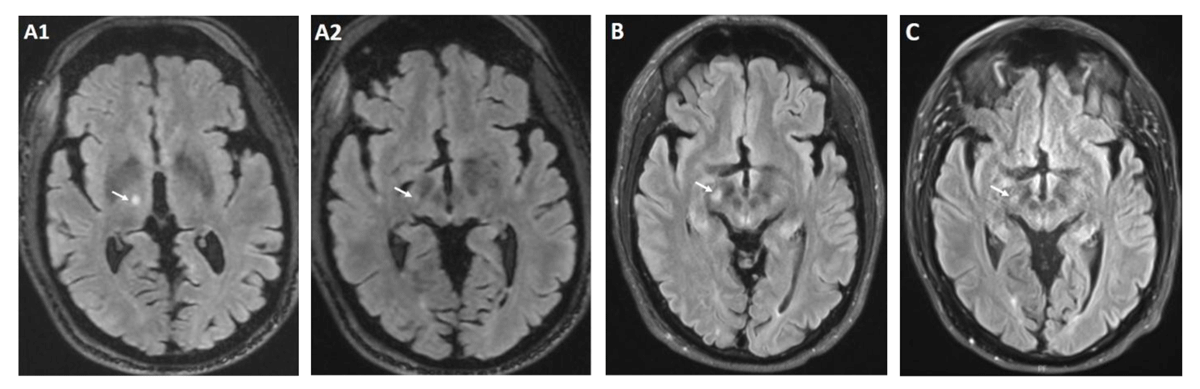

Figure 1

Brain MRI T2 FLAIR post procedure.

Immediately post procedure lesion at Vim (A1) with very slight extension to STN (A2) 1 month after procedure and onset of chorea with increased signal intensity involving the right STN (B) 8 months after procedure with near resolution of STN signal hyperintensity (C).

Given the medically refractory nature of his essential tremor, he underwent MR-FUS targeting the right ventral intermediate nucleus (Vim) of the thalamus (Figure 1A). The skull density ratio (SDR) was 0.63. The lesion site was localized 14 mm lateral to the midline, 25% of the AC-PC distance anterior to the posterior commissure (approximately 7.2 mm anterior) and 2.0 mm superior to the AC-PC plane. A total of six sonications were delivered, with a maximum energy of 9,444 Joules. Intraoperative temperatures ranged from 44°C to 58°C. The patient was assessed throughout the procedure for tremor improvement and potential adverse neurological effects, including paresthesia, weakness, ataxia, and dysarthria. Immediate post-sonication MRI demonstrated a well-circumscribed lesion within the right Vim, measuring approximately 240 mm3 in volume and located 3.63 mm from the margin of the lesion to the subthalamic nucleus (STN).

The procedure was uncomplicated, and he continued to remain off Aripiprazole in the post procedure period. Within one-week post-procedure, the patient reported involuntary movements of the left upper extremity. Due to concerns for post-procedural edema, an 8-day dexamethasone taper was initiated; however, there was no notable benefit. At the one-month follow-up, brain magnetic resonance imaging (MRI) demonstrated T2 hyperintensity in the right ventral thalamus, with signal abnormality extending inferolateral to abut the STN (Figure 1B). Neurological examination demonstrated marked improvement of the left-predominant tremor, with the FTM-TRS score decreasing from 6 pre-procedure to 1, indicating only mild kinetic tremor. However, there was new orofacial dyskinesias and left hemichorea involving proximal and distal muscle groups. There was also dystonic posturing of the left hand, which was present at rest and during ambulation (Video 1). These movements significantly impaired the patient’s quality of life, causing hand tightness from dystonic posturing and lip soreness due to oral dyskinesia.

Treatment options were carefully considered given the notable impact of these movements on the patient’s quality of life. After a thorough discussion of the potential benefits and risks, particularly in the context of the patient’s history of depression, tetrabenazine was initiated for symptomatic improvement. The decision was supported by the patient’s well-controlled mood symptoms, the medication’s established efficacy, and the availability of close clinical monitoring. Tetrabenazine 25 mg twice daily was initiated, resulting in significant improvement of the left hemibody movements, with only residual choreiform and dystonic movements of the left upper extremity and orofacial muscle groups (Video 1). This improvement was sustained through the eight-month follow-up. At that time, follow-up MRI showed a decrease in STN hyperintensity (Figure 1C). Despite this radiographic improvement, tapering tetrabenazine led to recurrence of left hemibody chorea, necessitating initiation of the previous dose.